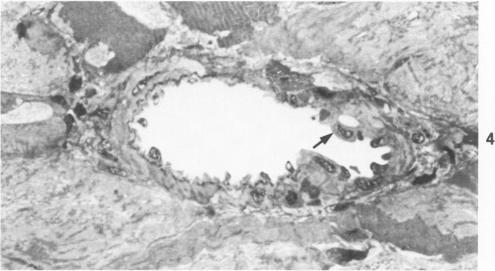

Adrenoreceptor blockade has been used to separate the actions of elevated blood pressure, angiotensin II, and catecholamines on the coronary vasculature and myocardium of rats. Twenty-two male Wistar-Kyoto rats received phentolamine (an alpha-receptor blocker, 10 mg/kg body weight) and/or propranolol (a beta-receptor blocker, 1 mg/kg body weight) followed by an infusion for 2 hours of angiotensin amide (1.7 micrograms/min/kg) or saline. Sections of left ventricle were examined by light and electron microscopy. Blood pressure was elevated only in animals receiving angiotensin II with or without propranolol. Epicardial arteries were devoid of lesions in all animals. Small intramural arteries and arterioles in the hypertensive animals exhibited vasoconstriction, endothelial cell vacuolization with bleb formation, and medial smooth muscle cell fragmentation and necrosis. Foci of irreversible ischemic or anoxic myocardial injury consisting of contraction zones and bands and translocated mitochondria with granular matrix densities were seen in angiotensin-infused animals. Similar but less severe myocardial changes were found in the animals pretreated with propranolol. Vascular lesions were also seen in animals receiving phentolamine, propranolol, and angiotensin II; but myocardial alterations consisted solely of areas with contraction zones. Vascular but not myocardial lesions were observed in animals that received angiotensin II and phentolamine. It is concluded that angiotensin II can produce vascular injury in the absence of elevated systemic blood pressure or catecholamine effects. In contrast, irreversible myocardial injury seems to depend upon the increased pressure and/or coronary artery vasoconstriction associated with angiotensin administration.

肾上腺素能受体阻断已被用于区分血压升高、血管紧张素 II 和儿茶酚胺对大鼠冠状动脉血管系统和心肌的作用。22 只雄性 Wistar-Kyoto 大鼠接受酚妥拉明(一种 α 受体阻滞剂,10 毫克/千克体重)和/或普萘洛尔(一种 β 受体阻滞剂,1 毫克/千克体重),随后输注血管紧张素酰胺(1.7 微克/分钟/千克)或生理盐水 2 小时。通过光学显微镜和电子显微镜检查左心室切片。仅在接受血管紧张素 II 且有或无普萘洛尔的动物中血压升高。所有动物的心外膜动脉均无病变。高血压动物的小壁内动脉和小动脉表现出血管收缩、内皮细胞空泡化并形成泡状突起,以及中层平滑肌细胞破碎和坏死。在输注血管紧张素的动物中可见不可逆缺血或缺氧心肌损伤灶,由收缩带和条带以及线粒体移位伴颗粒状基质密度组成。在预先用普萘洛尔处理的动物中发现了类似但较轻的心肌变化。接受酚妥拉明、普萘洛尔和血管紧张素 II 的动物也出现血管病变;但心肌改变仅由有收缩带的区域组成。在接受血管紧张素 II 和酚妥拉明的动物中观察到血管而非心肌病变。结论是,血管紧张素 II 在无全身血压升高或儿茶酚胺作用的情况下可产生血管损伤。相比之下,不可逆心肌损伤似乎取决于与血管紧张素给药相关的压力升高和/或冠状动脉血管收缩。